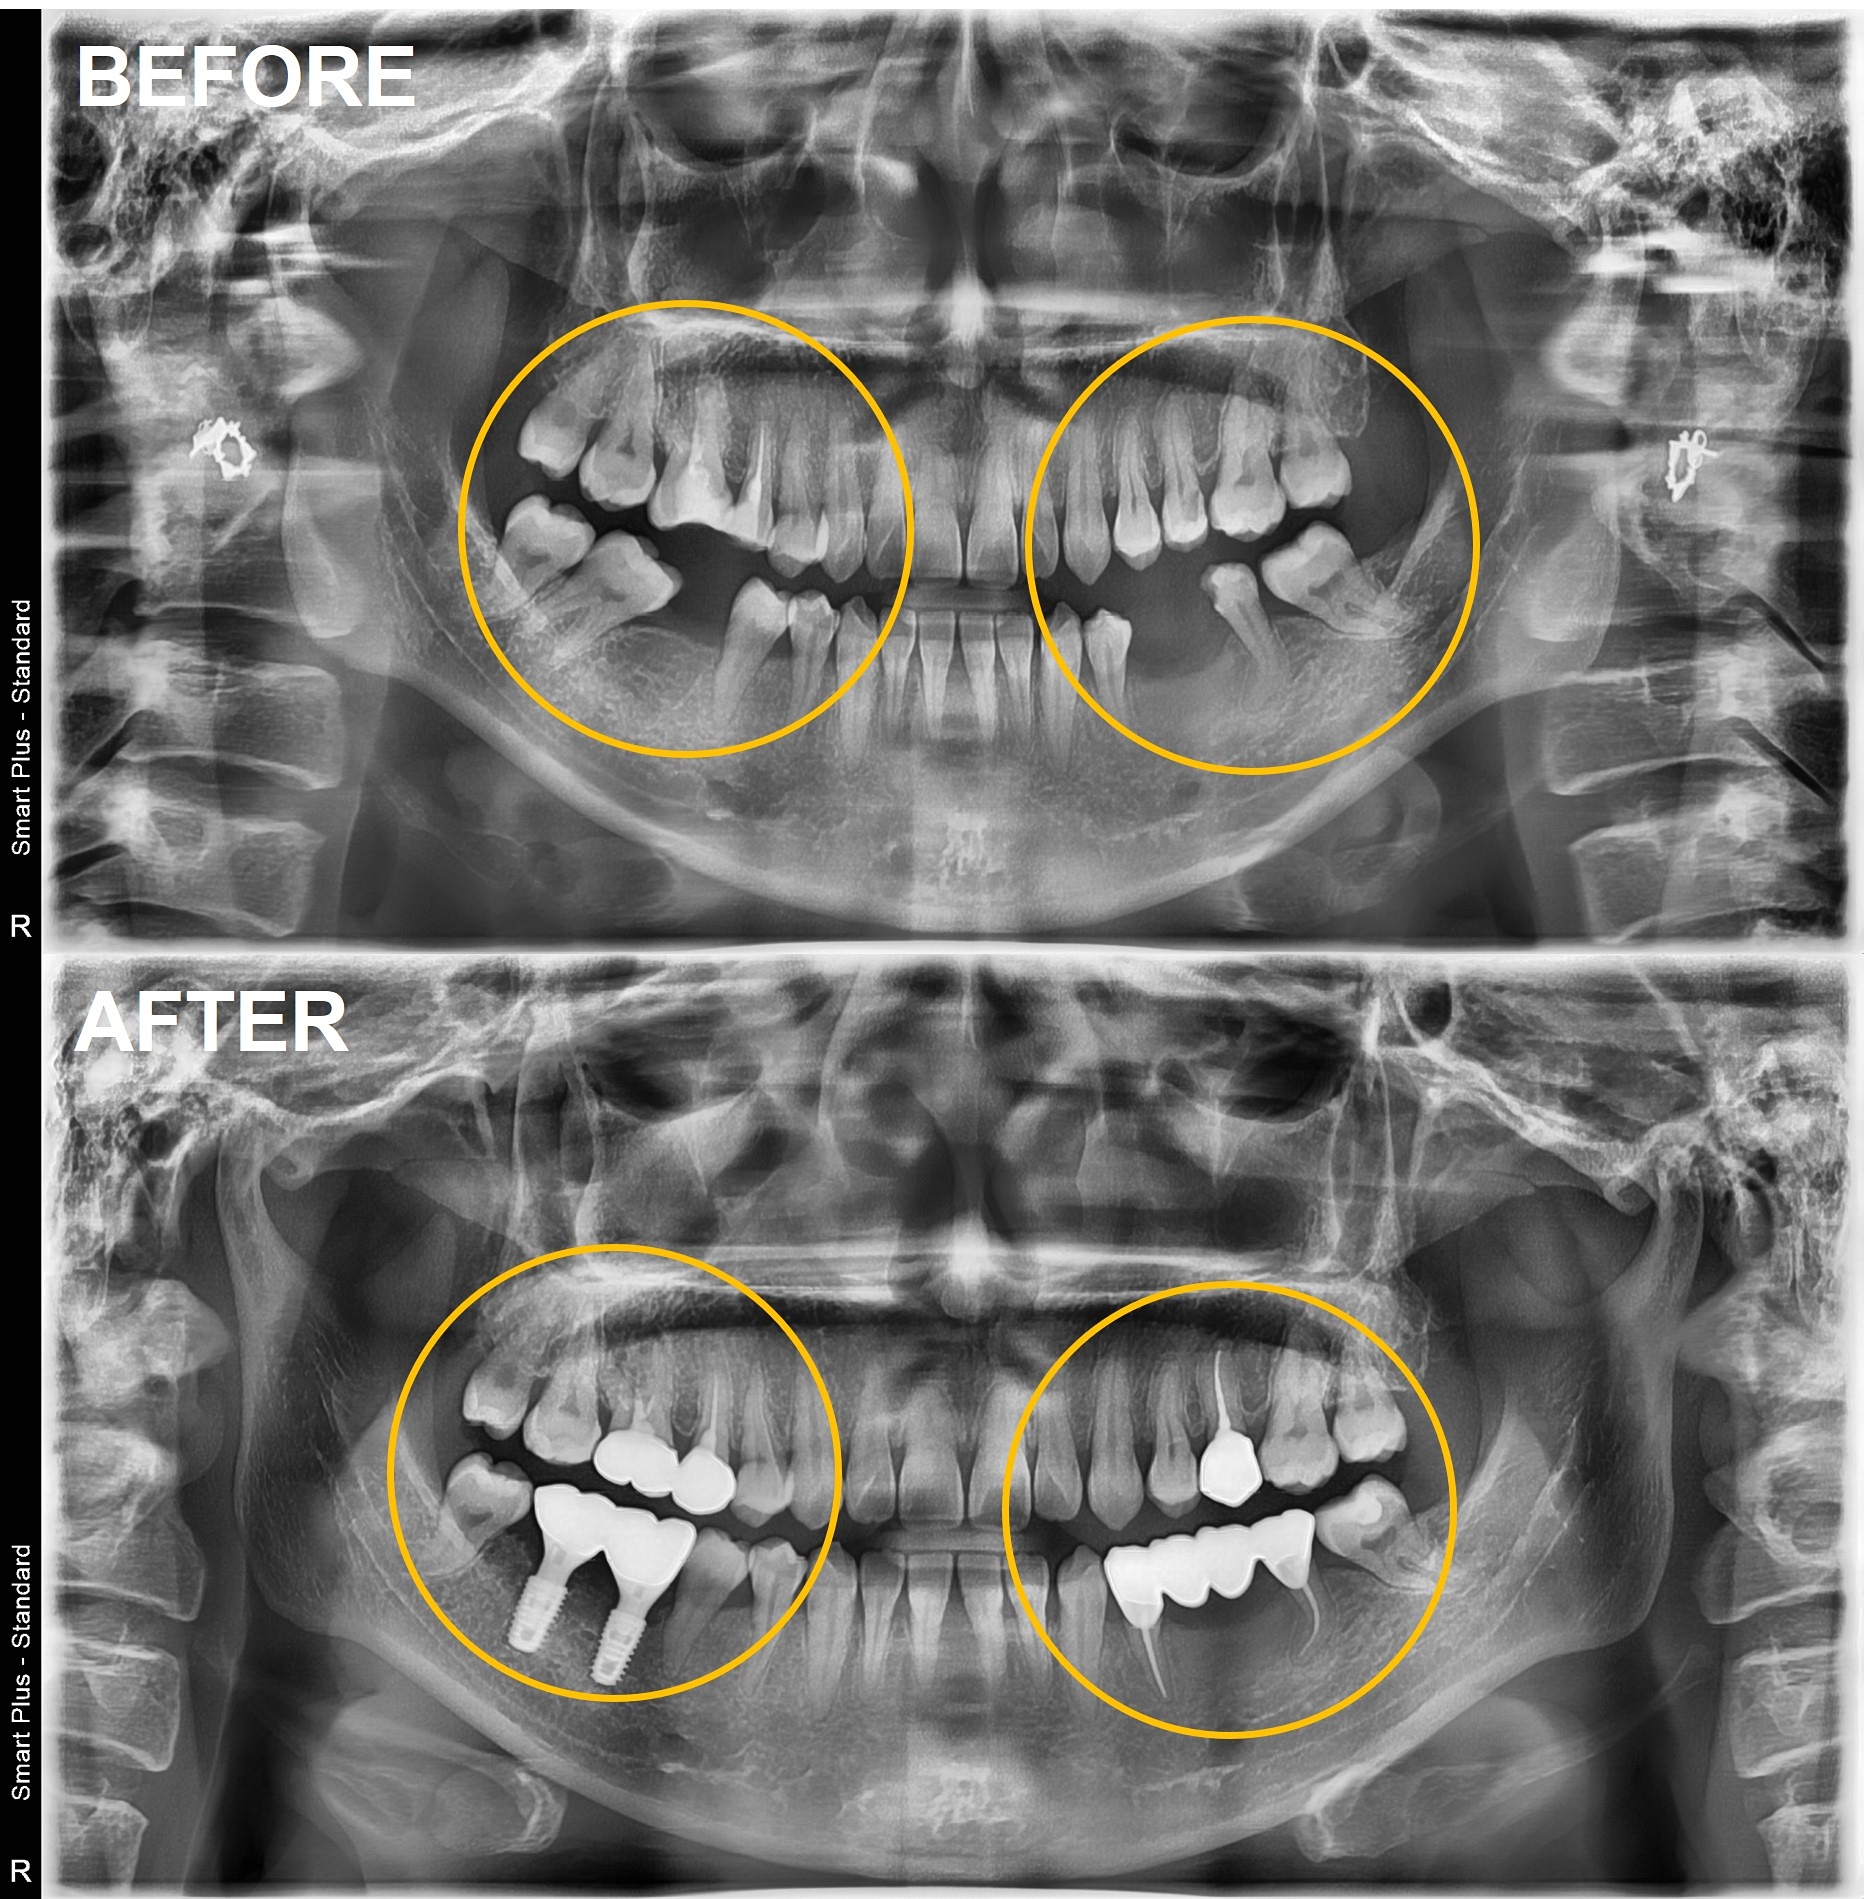

검단가온치과 임플란트 및 브릿지 치료

검단가온치과 임플란트 크라운 치료 전후 구강 사진

검단가온치과 50대 브릿지 교체 임플란트 전후 구강 사진